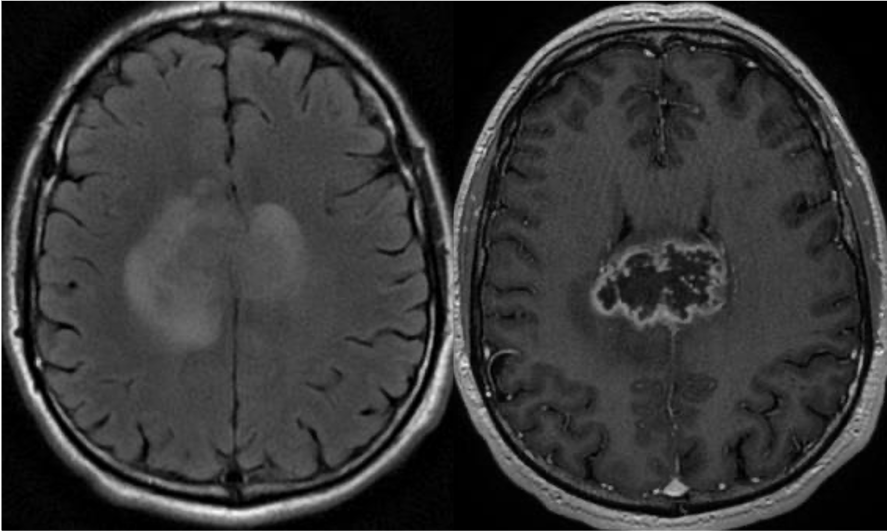

T1 images show mild T1 hypointense mass with cystic components, and minimal if any enhancement. So what’s the differential for a cortically based tumor in a child or young adult who presents with seizure? Pathology following resection c/w ganglioglioma.

This is less likely to be a glioblastoma, which is usually centered in supratentorial WM, with thick peripheral enhancement, and centrally necrotic.